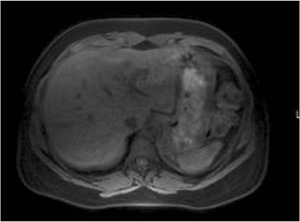

骨盤領域は脂肪組織に富むため,脂肪抑制が難しい部位の1つである。子宮病変検査へのH-sincパルスの適用例を図1に示す。本図から,安定して脂肪が抑制されていることがわかる。

図1 骨盤部画像例

a:H-sinc併用T1WI

b:T2WIc:H-sin

c:H-sinc併用DWI(b=50s/mm2)

d:H-sinc併用(b=800s/mm2)